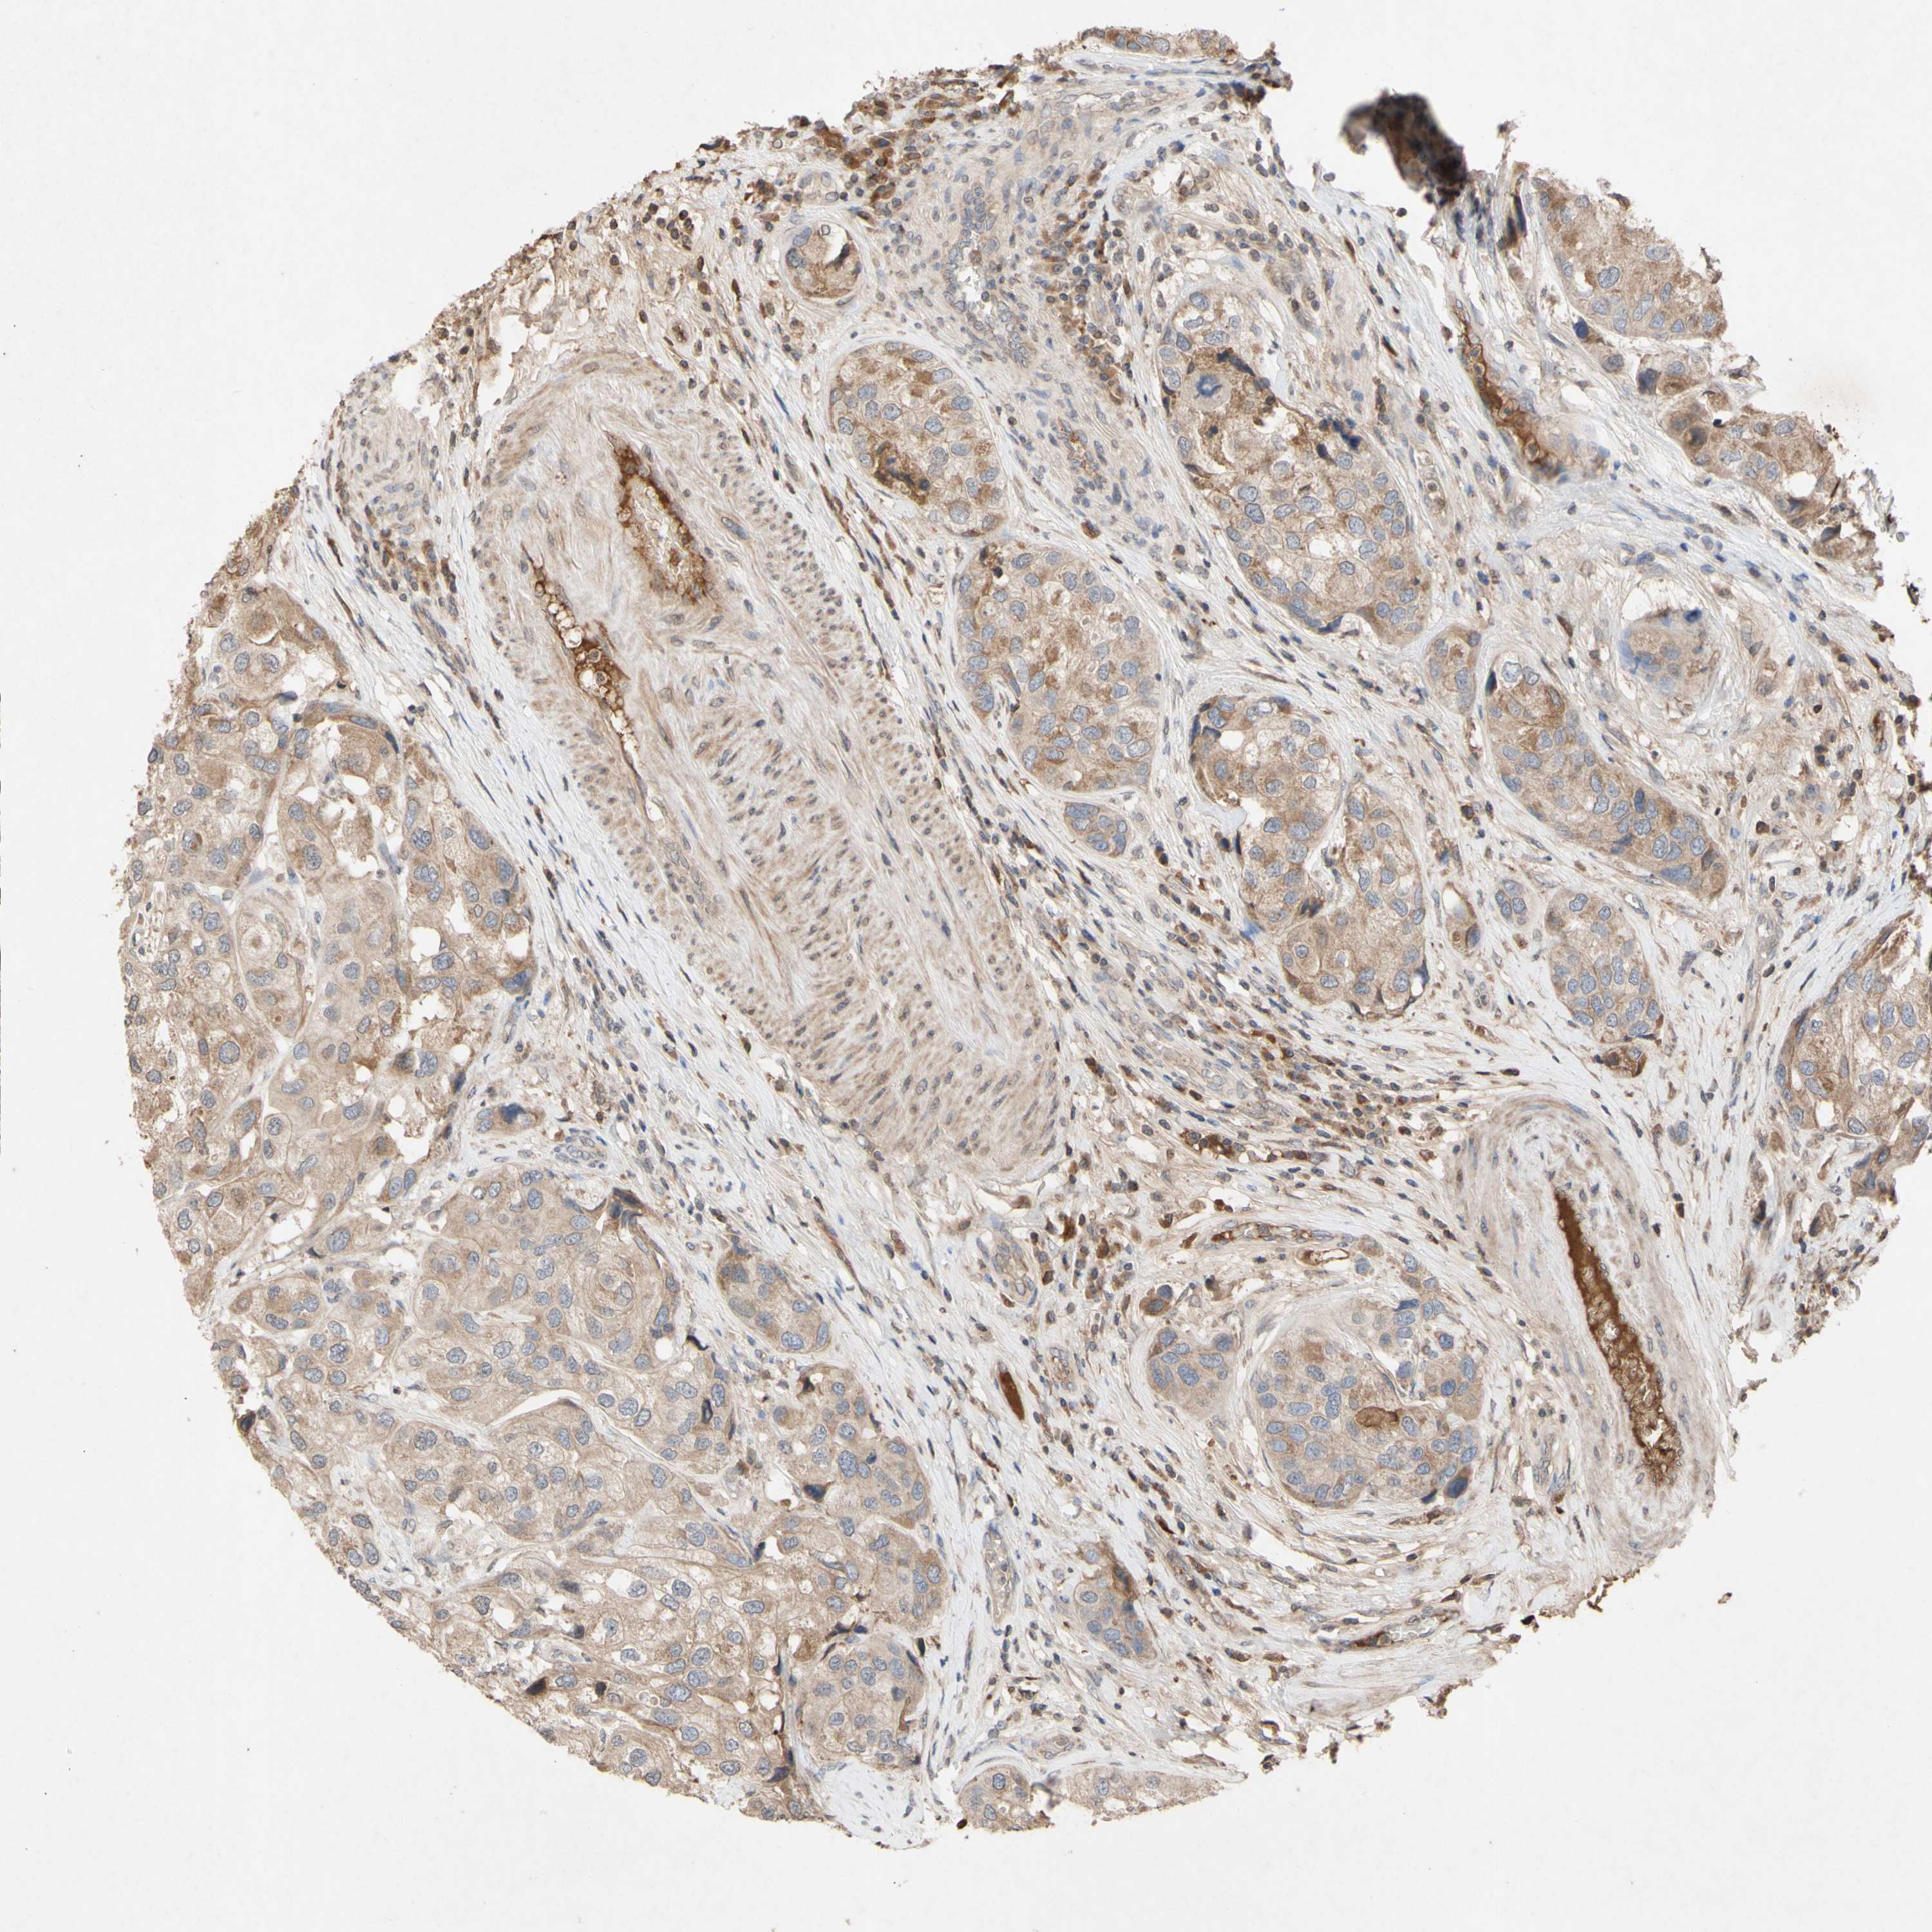

UROTHELIAL CANCER - Protein expressioni

A mouse-over function shows sample information and annotation data. Click on an image to view it in a full screen mode. Samples can be filtered based on level of antibody staining by selecting one or several of the following categories: high, medium, low and not detected. The assay and annotation is described here.

Note that samples used for immunohistochemistry by the Human Protein Atlas do not correspond to samples in the TCGA dataset.

Antibody stainingi

Antibody staining in the annotated cell types in the current human tissue is reported as not detected, low, medium, or high, based on conventional immunohistochemistry profiling in selected tissues. This score is based on the combination of the staining intensity and fraction of stained cells.

Each image is clickable and will lead to virtual microscopy that enables deeper exploration of all samples and also displays staining intensity scores, fraction scores and subcellular localization as well as patient and tissue information for each sample.

Antibody HPA011038

Antibody CAB009869

Urothelial carcinoma, Low grade

Urothelial carcinoma, High grade